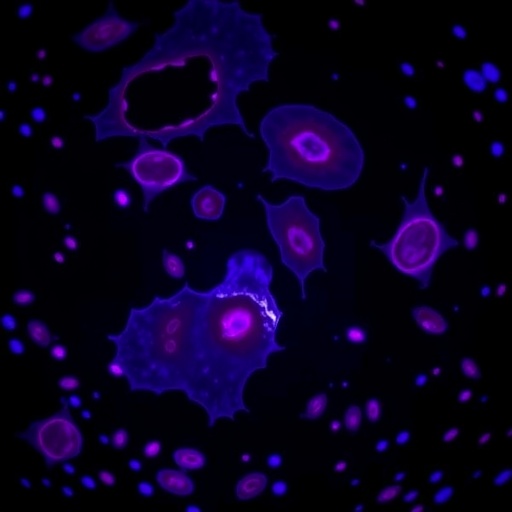

The researchers employed advanced single-cell RNA sequencing to profile the transcriptional landscapes of both CD4+ T cells and B cells in the tumor microenvironment. This high-resolution approach revealed signatures of chronic activation, including upregulation of costimulatory molecules and cytokines that enforce a positive feedback loop perpetuating B cell malignancy. These findings underscore the importance of cell-to-cell communication networks in tumor evolution.